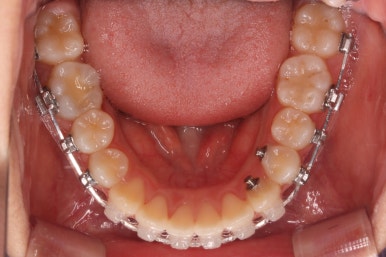

맨 우측 밑에 사진을 보시면 이가 하나 더 나와야 할 자리에(화살표) 앞뒤로 치아가 쓰러지면서 자리를 거의 없애버렸습니다.

따라서 이가 나올래야 나올 수가 없는 상태였습니다.

왼쪽 맨 위 사진을 보시면 아래 치열의 중앙이 한 쪽으로 쏠린 것을 알 수 있는데요. 역시 치아가 나올 자리가 없어지면서 치열이 쏠러버렸다는 것을 알 수 있습니다.

아래쪽이 더 시급하므로 브라켓 부착을 하여 가지런히 하기 시작했고 위쪽은 악궁확장장치를 입천장에 하여 위턱뼈를 가로로 넓혀주기 시작합니다.

치료 종료 후의 모습입니다.

치아들이 가지런하게 되었고, 나오지 못하던 치아도 잘 나와서 가지런해졌습니다.

해당 부위 앞뒤로 쓰러져 있던 치아들도 축이 바로 잡혔고, 자연스레 위-아래 치아의 중앙선도 맞아졌습니다.

치아가 잘 올라온 것을 볼 수 있습니다.